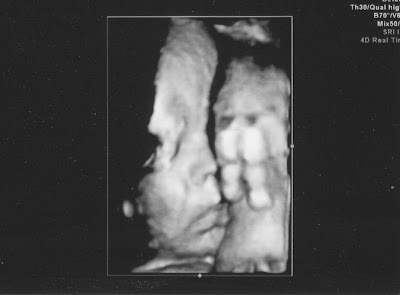

It's (Still) a Girl!

Whew, we're still expecting a baby Abigail! She was extremely cooperative and gave us an excellent shot at her girly parts - even I knew what I was looking at!

She's measuring at approximately 5 lbs. 4 oz. so far and everything else looks great.